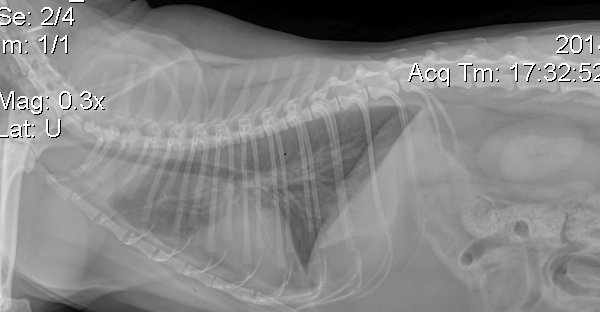

When the vet went over the x-rays with us in the examining room, she showed us a frontal view of his chest and pointed at the ghostly white stringy-looking things in his lung area. This bolstered her suspicion of asthma, and the next day, the analyzing radiologist confirmed it. When the vet gave us the images on the disc, we weren’t able to get back to that first view, but you can still kind of see it here: